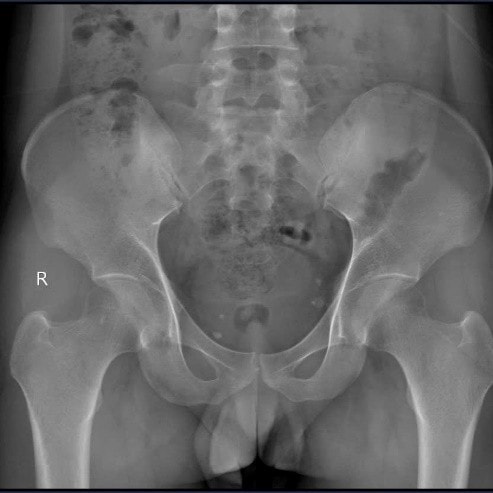

Tại Khoa Khám chữa bệnh theo yêu cầu và quốc tế, Bệnh viện E, ThS.BSNT Nguyễn Mạnh Quyết nhận thấy đây là trường hợp đau cột sống kiểu viêm – dấu hiệu then chốt gợi ý bệnh lý viêm khớp mạn tính. Bệnh nhân được chỉ định chụp X-quang khớp cùng chậu và làm xét nghiệm gen HLA-B27.

Kết quả cho thấy, bệnh nhân bị viêm khớp cùng chậu độ III hai bên, HLA-B27 dương tính, CRP và tốc độ lắng máu tăng. Trong khi đó, X-quang cột sống cổ vẫn chưa có biểu hiện dính khớp hay gai xương.

Từ các dữ kiện này, bệnh nhân được chẩn đoán xác định viêm cột sống dính khớp thể trục (theo tiêu chuẩn New York sửa đổi/ASAS 2009).